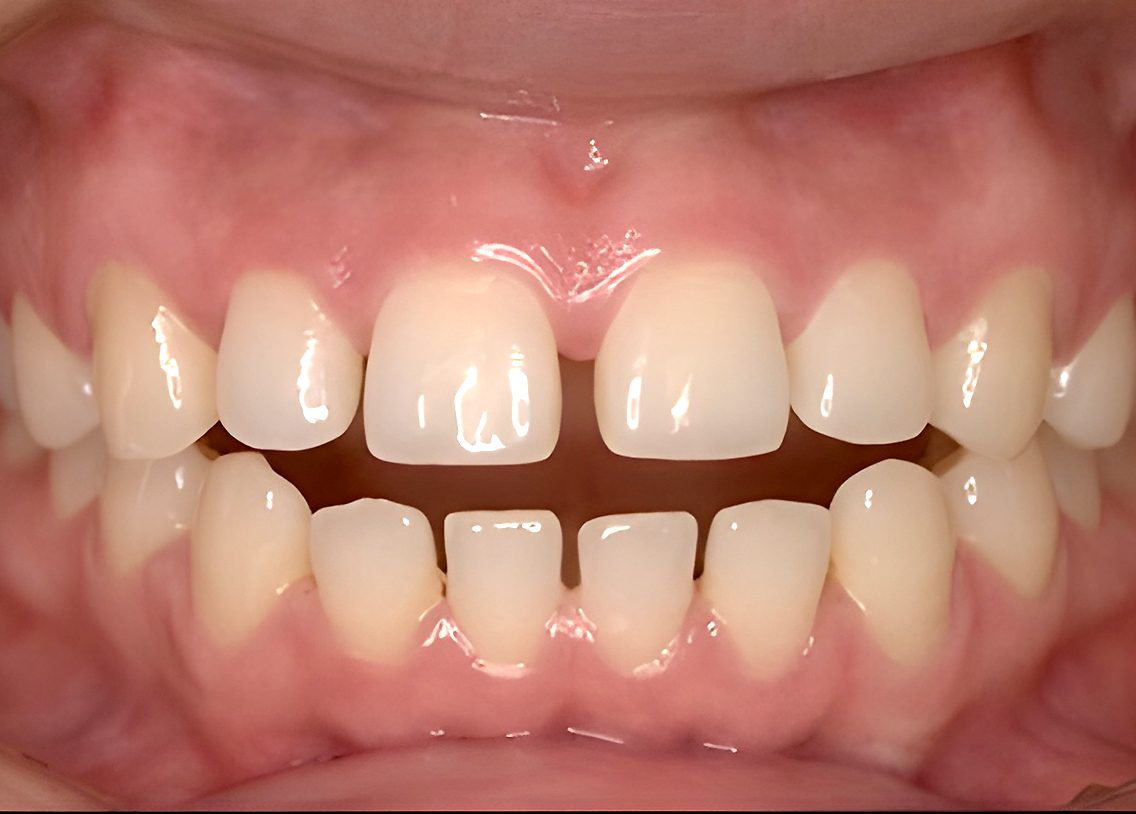

Before

after